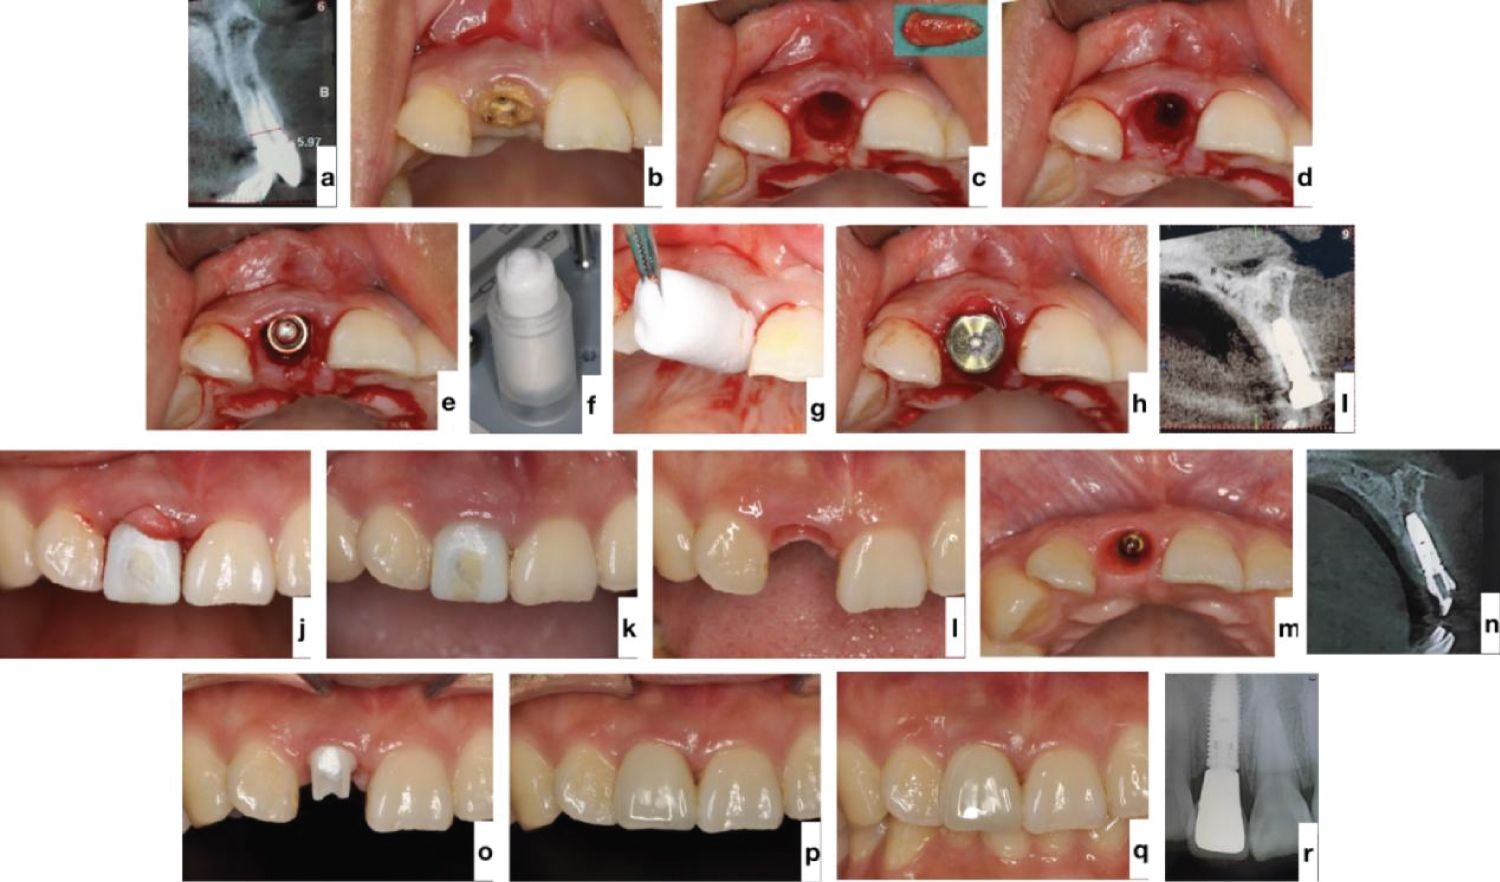

Since 2018, our teams have attempted to apply TERUPLUG ® in immediate implant placement procedure, aiming at obtaining an excellent buccolingual volume that is coincident with the contour of the tooth either in the anterior region or in the posterior region.

In our experience, when the implant is placed to the palatal aspect of the fresh tooth extraction socket, a buccal residual gap distance of about 2 mm will be left there. Then, place a wide flat contoured healing abutment, and adapt a suitable size TERUPLUG ® into U-shape and insert it against the abutment into the gap at the facial and interproximal side, filling the bone and soft tissue zones, to reserve the space for peri-implant hard- and soft-tissue [45]. Make sure that the TERUPLUG ® occupies the soft tissue zone to the height of the free gingival margin (FGM) and keep it out of contact with the threads of the implants, only in this way can TERUPLUG ® act as a scaffold to support the ridge contour profile (Figure 3). At the anterior zone, immediate restoration can be considered, acting both as the prosthetic seal and as the biomaterial protection and supporter during initial healing.

When the secondary implant stability is obtained after 3-6 months healing period, the provisionalization is removed, and the matured soft tissue contour is presented, a provisional prosthesis copying the maintained emergence profile is placed and then the final contour is transferred with a custom impression transfer technique. Finally we can obtain a restoration simulating the natural tooth emergence, thus guaranteeing more predictable results and simplifying the next stages of treatment (Figure 5).